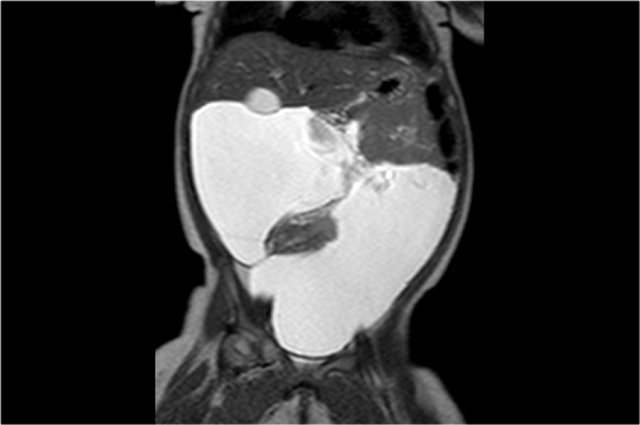

One-year-old boy was referred with a diagnosis of a cystic nephroblastoma.

Ultrasound detected a huge cyst in the middle of the abdomen.

When examined from the left flank with a high frequency linear array probe some parenchymal tissue was visible surrounding very dilated calyces. This is compatible with an extreme hydronephrosis.

At first it was thought that there were some solid parts in the cyst.

But when pressure was applied with the probe this proved to be debris.

MRI depicts the hydronephrosis with more overview.

The cause was a pyeloureteric stenosis.

The left kidney had 33% split renal function on renography.

A pyelum reconstruction was successfully performed.